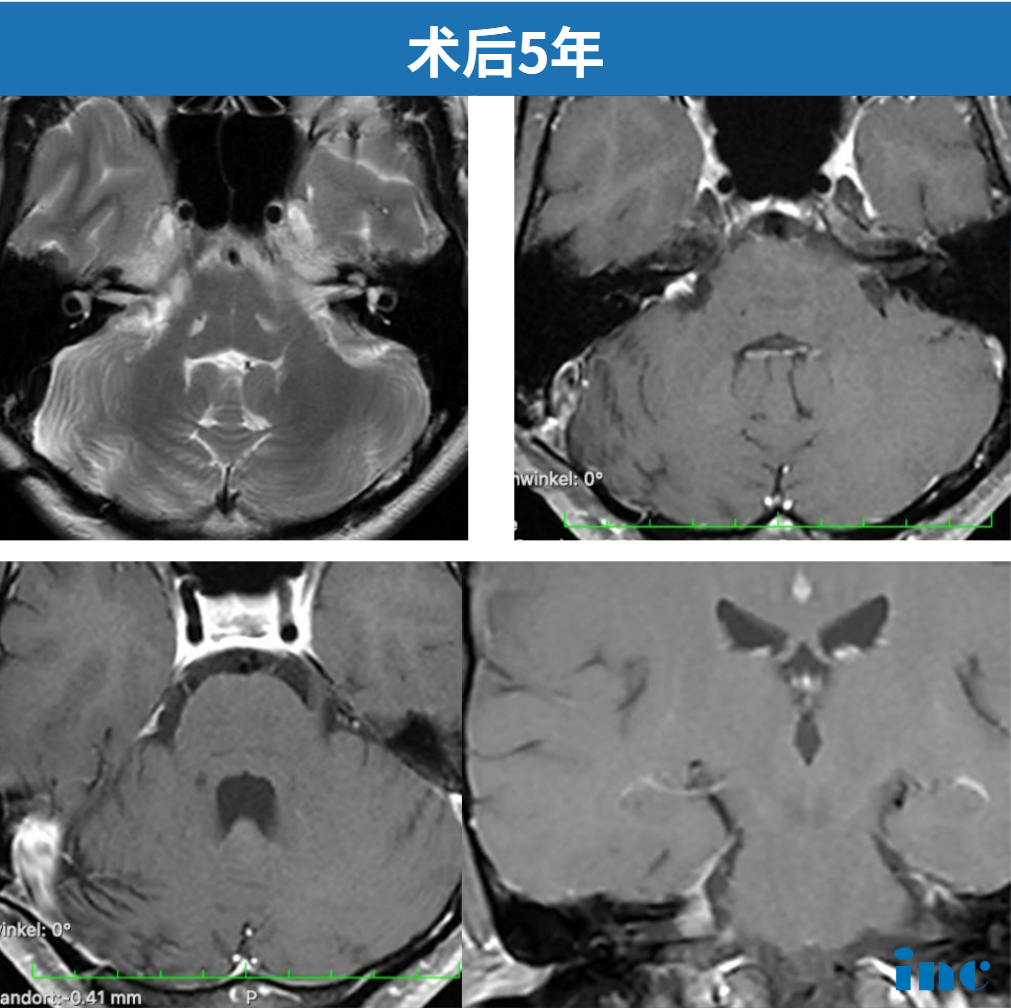

时光荏苒,2025年11月3日,阿岚术后第五年的最新核磁共振复查结果传来捷报:影像显示“非常理想”,未见肿瘤残留或复发。